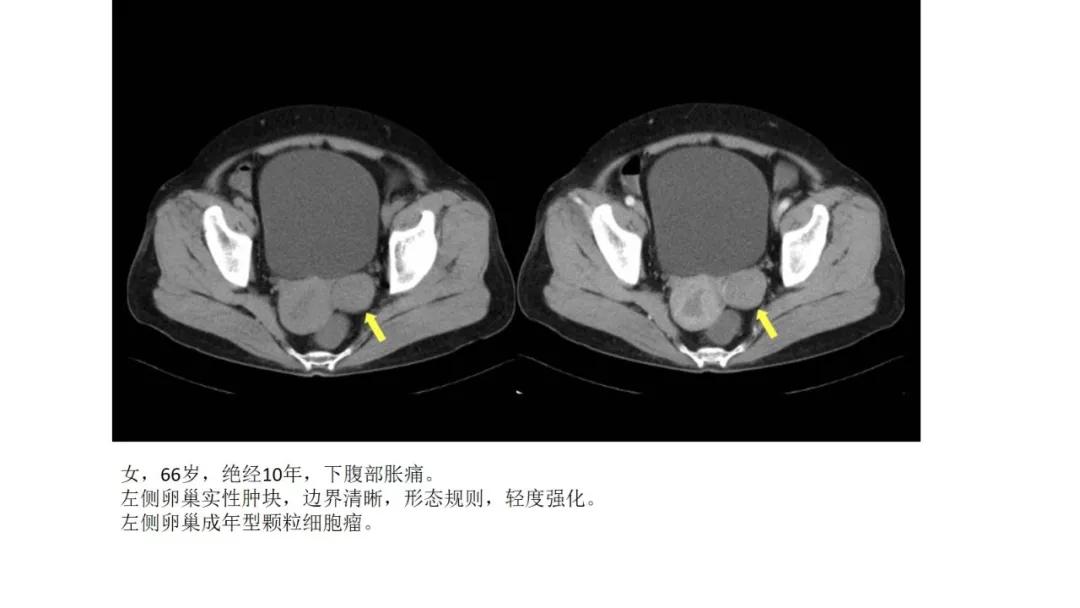

性索间质性肿瘤:较少见,良性多,多数肿瘤具有内分泌功能,可伴有内分泌症状及子宫内膜增生,内膜癌,乳腺疾病。多呈囊实性及实性肿块,界清,形态规则或欠规则,少有壁结节,多数呈实性伴有大片变性低密度改变,轻中度强化。

高雌激素症状:颗粒细胞瘤、卵泡膜细胞瘤(绝经期后出血及阴道不规则出血、性早熟、子宫内膜增生、乳房胀痛)

病理:颗粒细胞瘤